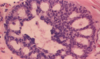

Epithelial hyperplasia (fibrocystic change)

Atypical epithelial hyperplasia (fibrocystic change)

Atypical epithelial hyperplasia (fibrocystic change)